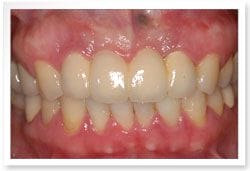

治療後

治療後-全口